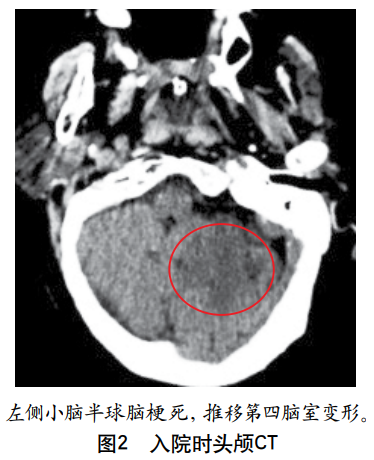

摘要:肥大性下橄榄核变性在临床上较为罕见,其典型临床表现包括腭肌阵挛、共济失调、声音嘶哑和眼部症状,而以四肢阵发性震颤为突出表现的患者则更为罕见,此类患者易被漏诊或误诊。本文报道1例继发于脑干(右侧脑桥和中脑)出血、以四肢阵发性震颤为突出表现的肥大性下橄榄核变性患者,介绍其诊断、治疗及随访情况,并结合相关文献探讨此类患者的临床特点,总结其解剖基础、影像学表现、诊断与治疗要点,以提高临床医师对该病的